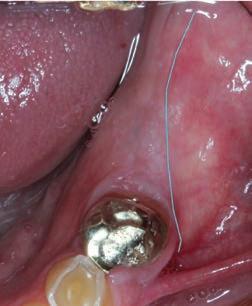

Although low trauma extraction techniques have been discussed in a previous Masterclass, it is relevant to emphasize the importance of not approximating the soft tissue margins over a tooth socket by suturing. Leaving the extraction socket open for healing to occur will create more attached gingiva at the future implant site (Fig. 3). This newly formed gingiva can then be moved buccally by placing the crestal incision more towards lingual during implant placement or exposure.

Figure 3: Healed extraction site 3-months after low trauma extraction, with adequate amount of attached keratinized tissue for implant placement.

Epithelial palatal transplant (EPT) to increase the width and thickness of keratinized tissue around implants

Grafting of soft tissue can be done at three different time periods: before implant placement (Figs 4a-c), at the same time (Figs 5a-c) or after implant placement (Figs 6a-c). Experienced clinicians may opt to perform an EPT simultaneously with implant placement as this saves multiple surgical procedures and is more cost effective. This is shown in Fig 5 and also in the video link provided. This is a complex procedure which should not be attempted by inexperienced clinicians. Grafting before the implant placement is the more predictable procedure and provides a better implant environment to place the implant.

Figure 4a: Pre-operative view showing alveolar mucosa almost to crest of ridge Figure 4b: Graft secured with vestibular deepening done as well Figure 4c: Post-operative view showing graft healing after 8 weeks

Figure 5a: Preoperative view with mucogingival line shown in blue Figure 5b: Simultaneous implant placement and epithelial palatal transplant Figure 5c: Postoperative view with crowns placed. Rugae can be seen but, as it is not an aesthetic area, this is of no consequence Figure 6a: Implants placed years before with peri-implantitis and no keratinized attached tissue buccal of implants. Figure 6b: Graft providing keratinized tissue as well as vestibuloplasty. Patient can wear prosthesis but it has to be eased to ensure no pressure on graft Figure 6c: Postoperative view showing a stable attached peri-implant keratinized tissue and vestibular deepening giving better access for plaque control